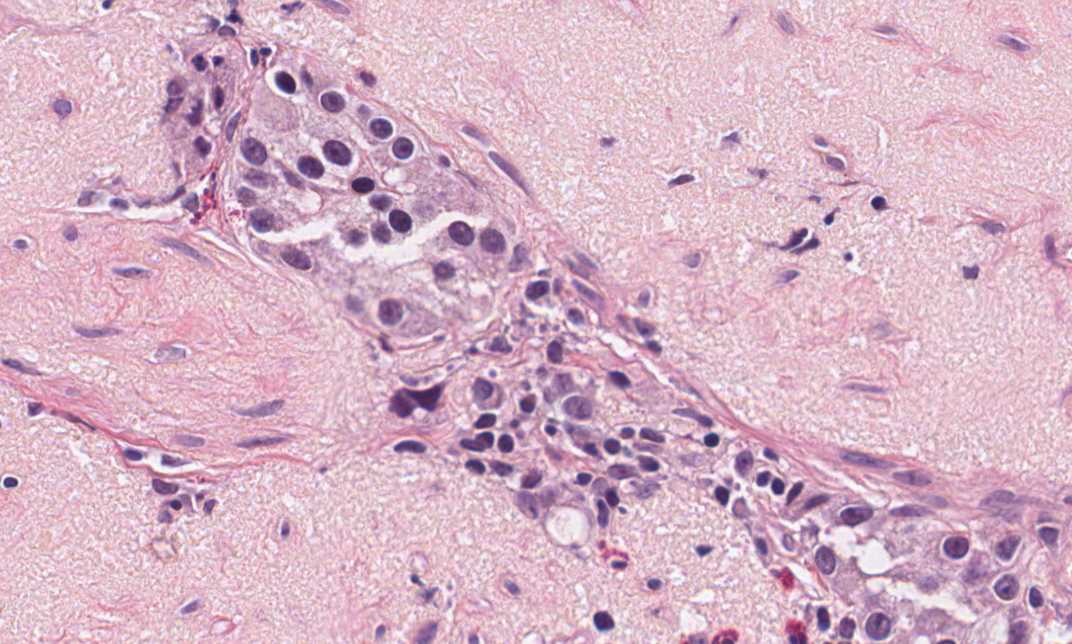

Hematoxylin & eosin

High magnification: A high magnification image shows round, and rather monontonous nuclei with prominent nucleoli and "salt and pepper" like chromatin. Although some adenocarcinoma can have this kind of nuclei, the nuclear features raise a serious concern of neuroendocine tumor.

• The myxomatous stroma in this case is likely to suggest mucin producing adenocarcinoma on the first glance. However, there is no mucin production by tumor cells on hematoxylin and eosin stain. On the other hand, the monotonous, round nuclei and the organoid like arrangement of tumor cells suggest neuroendocine carcinoma.